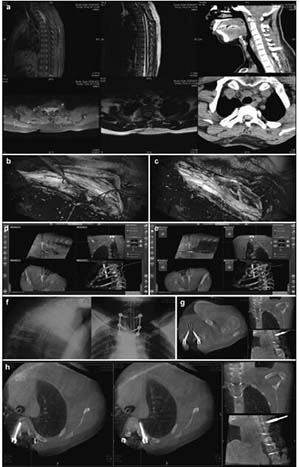

20171023161255 Figure 2 Preoperative, intraoperative, and postoperative images of patients in the thoracic intraspinal meningioma resection and pedicle screw fixation group. (a) Cervical thoracic vertebrae computed tomography shows a high-density tumor shadow in the thoracic spinal canal (T1-T4). Magnetic resonance imaging shows T2 image isointensity in the spinal canal (T1-T4). An enhanced scan shows a significantly enhanced area located in the ventral spinal cord that has invaded the intervertebral foramen. (b) Intraoperative microscopy shows a spinal cord ventral tumor, originating in the dura mater. (c) Intraoperative microscopy shows nearly total resection of the spinal cord ventral tumor, with the spinal cord remaining intact. (d, e) Intraoperative T2 pedicle screw implantation is performed under real-time navigation. The entry direction, angle, and depth of the screw is according to the navigation plan. (f, g, h) After screw implantation, an O-arm two-dimensional lateral scan shows good screw positioning. The O-arm three-dimensional scan found that the T1 bilateral pedicle screws are well positioned and do not penetrate the bone cortex. The T4 left pedicle screw position is also good. The left pedicle screw is in the lateral vertebrae, and no lung injury is seen between the vertebral body and rib. The screw position was not adjusted intraoperatively because it is within the acceptable range.

20171023161341 Figure 3 Preoperative, intraoperative, and postoperative images of the lumbar spinal canal of a patient in the internal and external schwannoma resection and pedicle screw fixation group. (a) Lumbar computed tomography (CT) shows an L4-5 intraspinal isodense tumor and a damaged L4 left pedicle and vertebral body. Magnetic resonance imaging (MRI) shows an iso- and hyperintensive signal tumor at L4-5 on the intraspinal T2 image. It is located on the left side of the spinal canal and has invaded a vertebral body and the intervertebral foramen. (b) Fusion of the CT and MRI images, in combination with an intraoperative O-arm and navigation technique, identifies the tumor site and border. (c) Intraoperative L5 pedicle screw implantation is performed under navigation. The screw’s direction, angle, and depth can be seen to match the navigation plan. (d) After screw implantation, an intraoperative O-arm two-dimensional lateral scan shows that the screw position is good. (e) An O-arm three-dimensional (3D) scan shows that the L3 pedicle screw position is good, and does not penetrate the bone cortex. (f) An O-arm 3D scan shows that the L5 left pedicle screw position moves away from the vertebral body and penetrates the rough pedicle bone cortex; (g) An O-arm scan was conducted again to introduce the navigation system as part of the correction of the L5 left pedicle screw, getting it to a good position. (h) An O-arm 3D scan shows that the L4 right pedicle screw position is good. It does not penetrate the bone cortex. Screws are difficult to implant in the left pedicle and vertebral body due to tumor invasion. (i) A lateral lumbar radiography scan, 7 days postoperatively, shows firm screw fixation and good positioning.